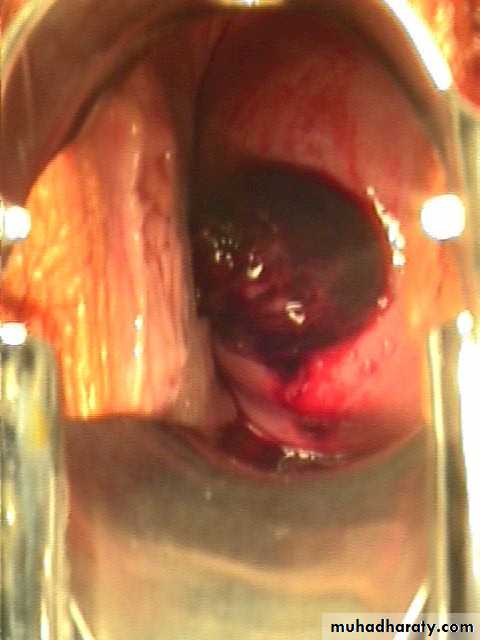

Incomplete abortion:

Symptoms are the same as for inevitable abortion but some products of conception are passing from uterus and part of product of conception retained in the uterus or cervical canal, a situation that causes ongoing cramping and excessive bleeding with danger of shock and sepsis.

Incomplete abortion

Symptoms:1. uterine bleeding which is varies may be severe to cause hypovolemia or mild

2.history of passing part of conception (Women describe the product of conception as looking like pieces of skin or liver).

Sign:1.Uterus may be smaller than expected for period of amenorrhea.

2.Cervix is open.

3.Speculum examination reveals dilated internal os and tissue within the endocervical canal or vagina.

4.Bleeding may be heavy.

Incomplete abortion with products of conception passing through the dilated cervical os